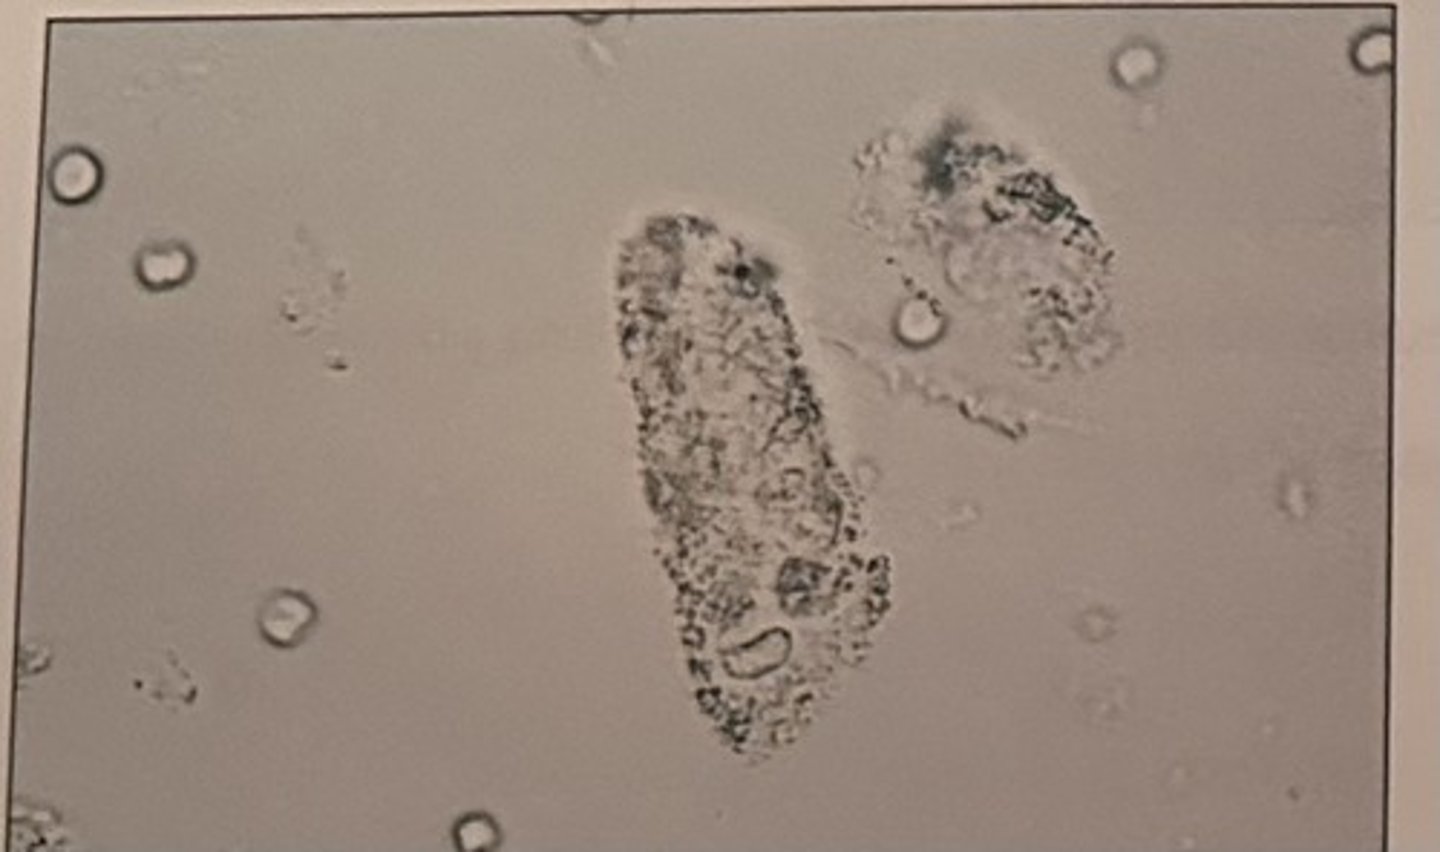

Identify the elements seen in the photomicrograph:

a. RBC

b. urothelial cells

c. WBCs

d. tyrosine crystals

What is the most likely diagnosis given the microscopic finding?

a. cystitis

b. pyelonephritis

c. glomerulonephritis

d. nephrotic syndrome